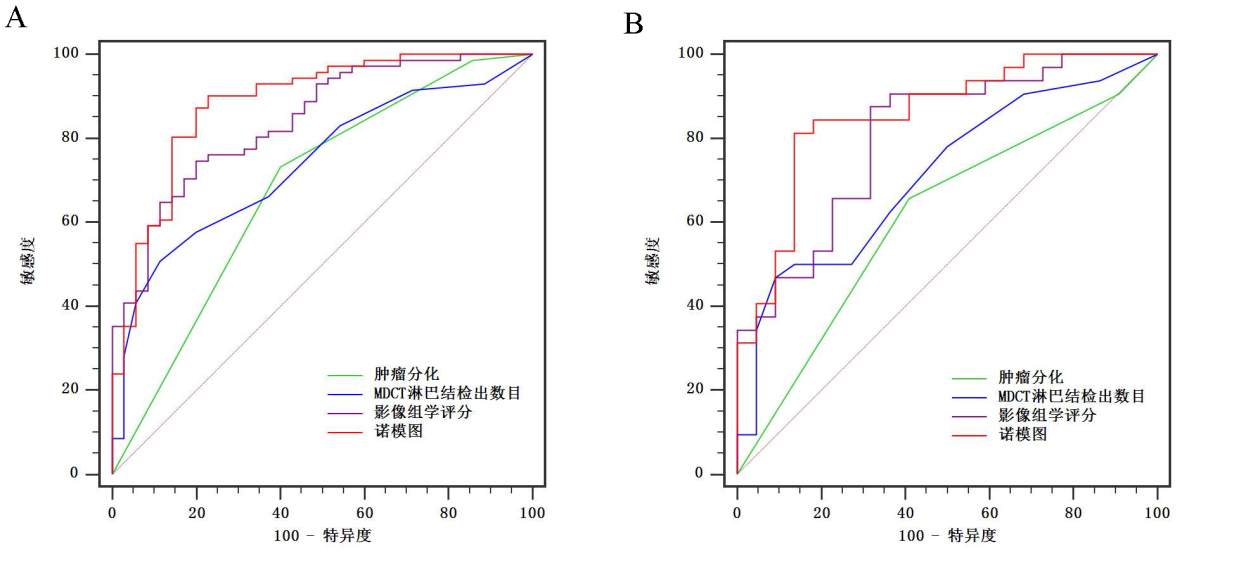

基于MDCT影像组学特征的模型对于预测胃癌淋巴结转移具有较高的准确度��,可为胃癌的个体化诊治提供基础信息����,有助于提高对临床决策的信心����。此外���,基于影像组学的模型还具有对胃癌患者预后分层的潜力���。

图6 (A)训练队列和 (B)验证队列中基于影像组学的诺模图及各指标单独预测胃癌淋巴结转移的ROC曲线比较